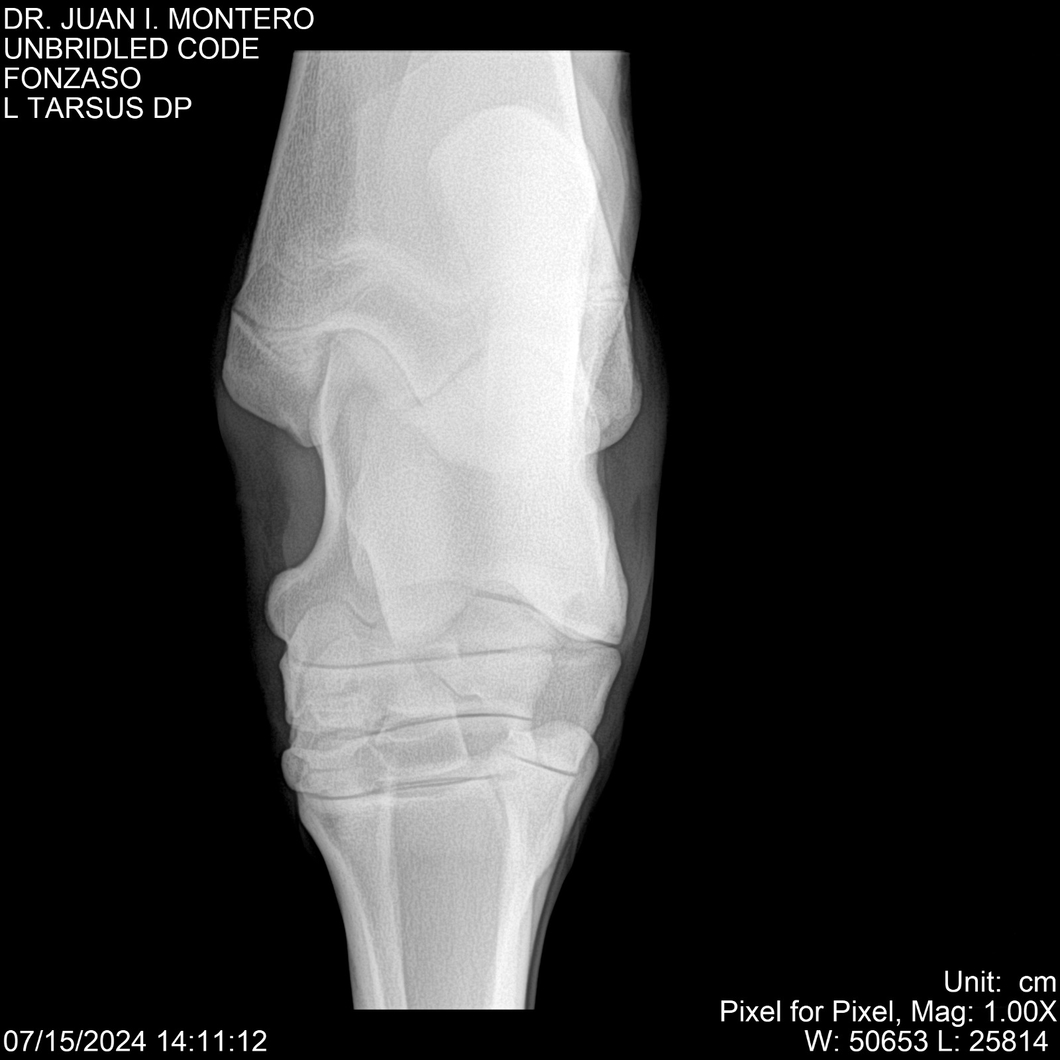

• Empresa: Abelenda N. R., Walter Hugo